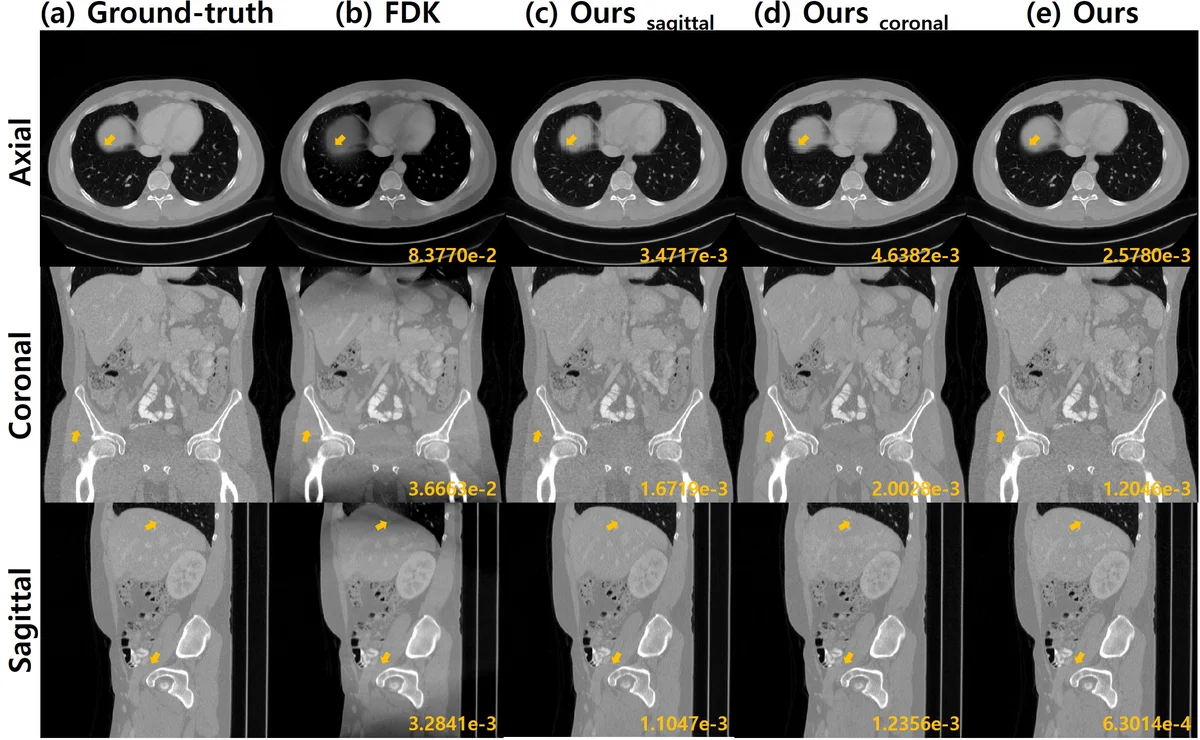

본 논문은 원뿔빔 CT의 원형 궤도에서 발생하는 콘빔 아티팩트를, 미분 역투영(DBP) 도메인에 설계된 인코더‑디코더 CNN을 이용해 데이터‑드리븐 방식으로 복원한다. DBP 데이터를 코롤라 및 시상면으로 분리하고, 각 면에서 Hilbert 변환에 기반한 비선형 디컨볼루션을 학습한 뒤, 스펙트럼 블렌딩으로 두 결과를 결합해 누락된 주파수 영역을 보완한다. 실험 결과, 기존 모델 기반 반복 재구성보다 연산량은 크게 줄이면서도 재구성 품질이 우수함을 확인하였다.

하지만 단일 평면에서 복원된 결과는 해당 평면에 특화된 누락 주파수 영역을 그대로 남긴다. 이를 보완하기 위해 저자들은 코롤라와 시상면 두 방향에서 각각 DBP‑CNN을 적용한 뒤, 2‑D 푸리에 변환을 통해 스펙트럼 영역을 얻고, “보우‑타입” 가중 마스크(w)로 각 방향의 누락 주파수를 억제한다. 최종 복원은 f_com = F⁻¹{ w·F{f_cor} + (1−w)·F{f_sag} } 형태로 두 스펙트럼을 혼합함으로써, 두 방향이 서로 보완하는 효과를 얻는다. 이 스펙트럼 블렌딩은 특히 고각도 원뿔빔에서 발생하는 스트리크 아티팩트를 크게 감소시킨다.

실험에서는 시뮬레이션 데이터와 실제 측정 데이터를 모두 사용했으며, 훈련은 노이즈가 없는 시뮬레이션으로 진행했음에도 불구하고, 노이즈가 섞인 실제 데이터에 대해 뛰어난 일반화 성능을 보였다. 또한, 동일한 네트워크를 다양한 콘빔 각도에 적용했을 때 재학습 없이도 안정적인 복원을 수행한다는 점에서, 학습된 필터가 물리적 기하학적 변동성을 내재적으로 학습했음을 시사한다. 전체 파이프라인은 전통적인 FDK + 반복 재구성 대비 10배 이상 빠른 실행 시간을 기록했으며, PSNR·SSIM 등 정량적 지표에서도 현저히 우수한 결과를 얻었다.